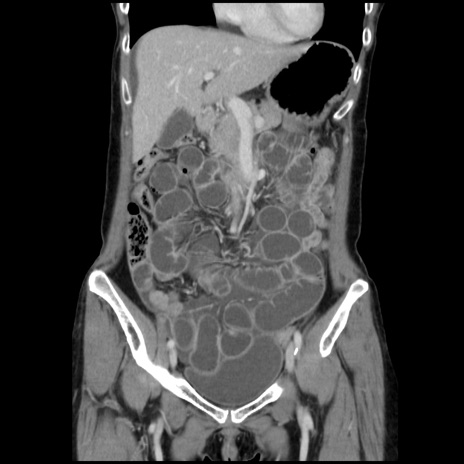

症例32(冠状断像)

【症例】40歳代 女性

【主訴】上腹部痛、嘔気・嘔吐

【現病歴】約9時間前頃から急に上腹部痛、嘔気、嘔吐が出現。改善しないため救急要請。

【既往歴】子宮頚癌(広汎子宮全摘術、放射線療法)、腸閉塞

【身体所見】腹部:平坦、軟、腸雑音亢進、上腹部を中心に腹部全体に圧痛あり。

【データ】WBC 8400、CRP 0.03